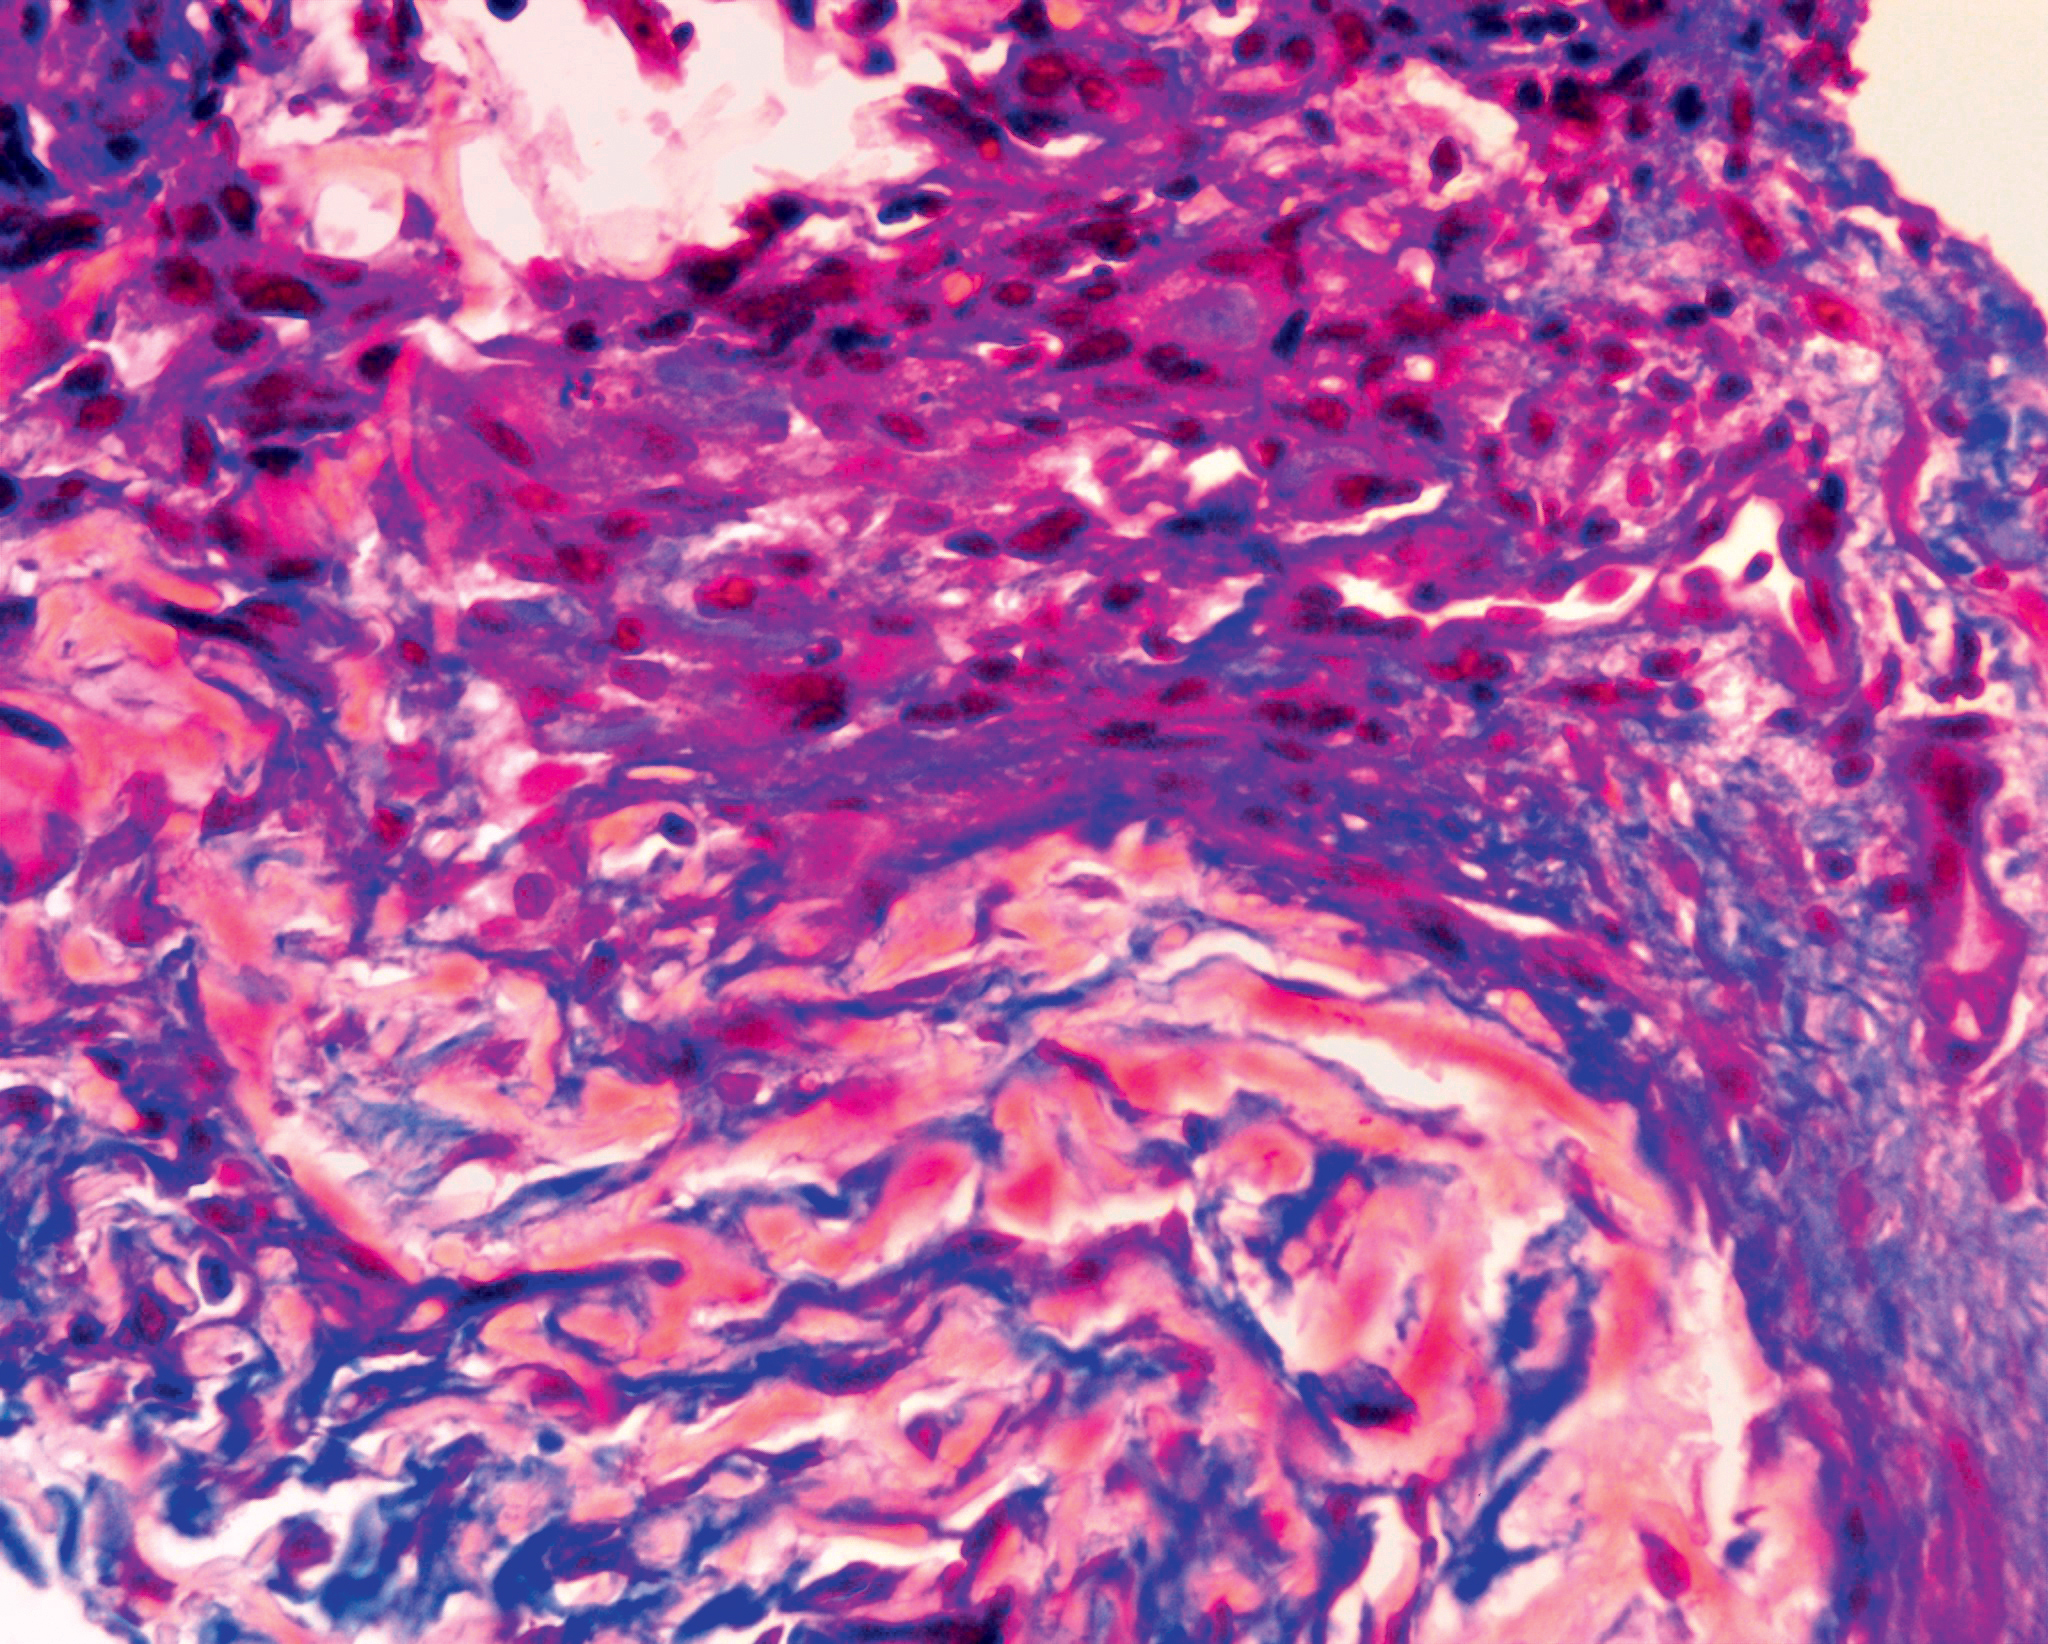

Figure 6.

A - four ring-shaped foci on the left shin, the maximum focus is 2.5 cm in diameter, arrow 1 indicates the location of the biopsy.

B - dermatoscopic picture of rashes on the border with healthy skin.

C - histological microphotograph of skin lesion: arrow 2 indicates keratin cyst with basophilic substance inside. Hematoxylin and eosin, x200

D - histological microphotograph of skin lesion: arrows 3 indicate giant multinuclear cells among the inflammatory infiltration. Hematoxylin and eosin, x200